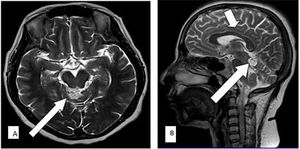

Case History: 75-year-old male with complaint of occasional headaches for last two years.

Published: August 19th 2014 | Updated: